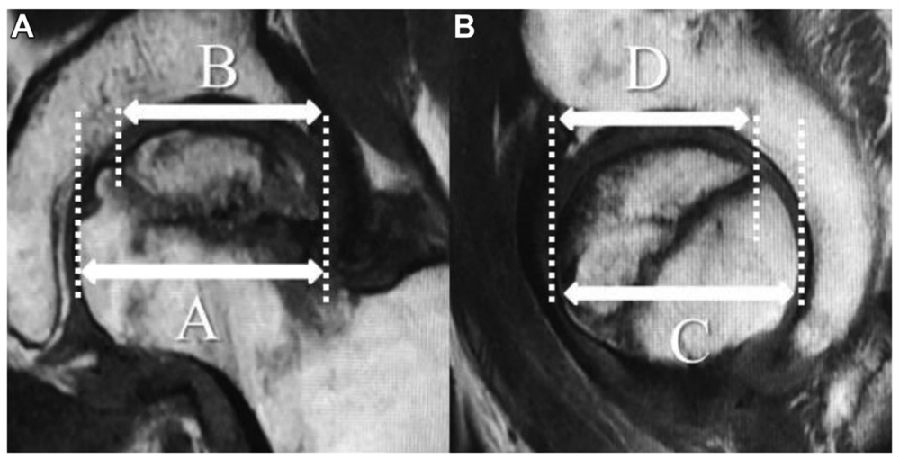

图8. 使用冠状面和矢状面T1磁共振成像(MRI)研究坏死病变

(A)利用冠状MRI上股骨头最大内外侧直径 A与坏死病灶最长内外侧长度B之比。(B)矢状面MRI上使用股骨头最大AP直径C和坏死灶最长前后长度D之比。